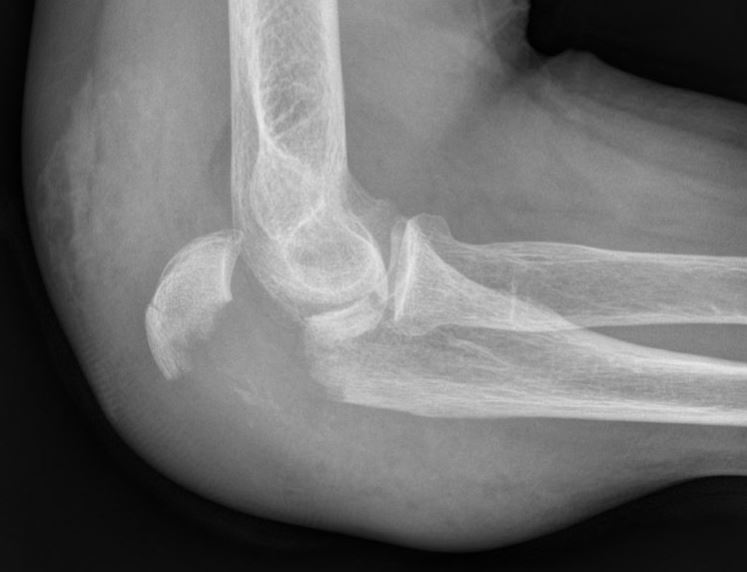

Bij een breuk van het olecranon is er vaak pijn en zwelling ter hoogte van de elleboog en een onvermogen om de arm te strekken. Een Röntgenfoto kan de diagnose bevestigen.